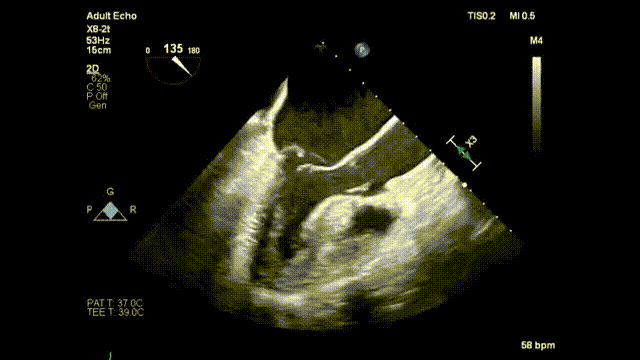

59岁朱女士患二尖瓣关闭不全10多年,并伴有胸闷、气喘、心悸。术前超声诊断:二尖瓣后叶P2节段脱垂、腱索断裂伴重度反流、肺动脉高压。经上海复旦大学附属中山医院王春生教授、魏来教授团队综合评估分析,决定使用北京迈迪顶峰医疗科技股份有限公司研发的“E-Chord™二尖瓣修复装置”进行腱索重建手术。

手术正式开始,魏来教授和杨晔医生在心超诊断科董丽莉教授、赵维鹏教授的协助下,仅一个多小时就顺利完成了E-Chord™的穿刺“发射任务”。4根人工腱索被送入朱女士的心脏,准确锚定在二尖瓣脱垂病变区域。然后在超声引导下精确调整人工腱索长度并固定在心尖,从而恢复了朱女士正常的二尖瓣关闭功能。手术完成后朱女士二尖瓣反流立即由重度减少为微量;同时左房平均压明显改善,由术前42mmHg下降到24mmHg。手术全程在超声引导下进行,操作便捷可控,无放射线,心脏不停跳,无需体外循环,创伤小,不出血,恢复快。患者术后2小时即拔除气管插管并返回病房,第二天即可下床活动。

术前二尖瓣重度反流